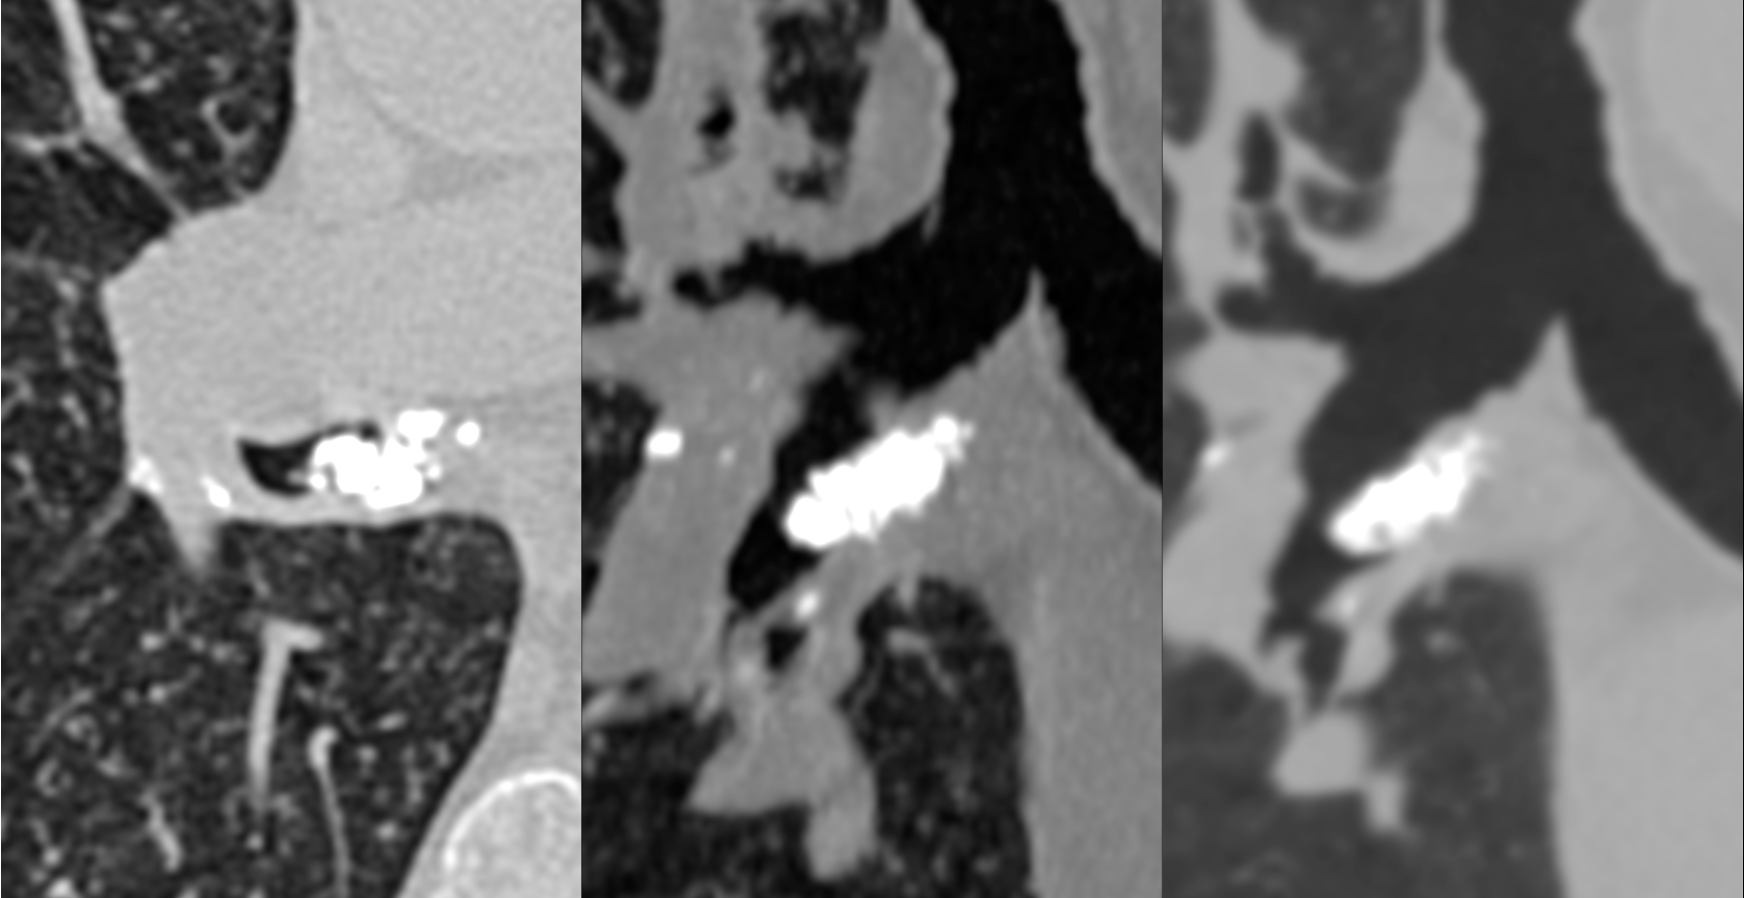

71-years old man with fever.

CT shows miliary nodules likely due to miliary tuberculosis.

It also shows a calcified subcarinal node extending into the intermediate bronchus.